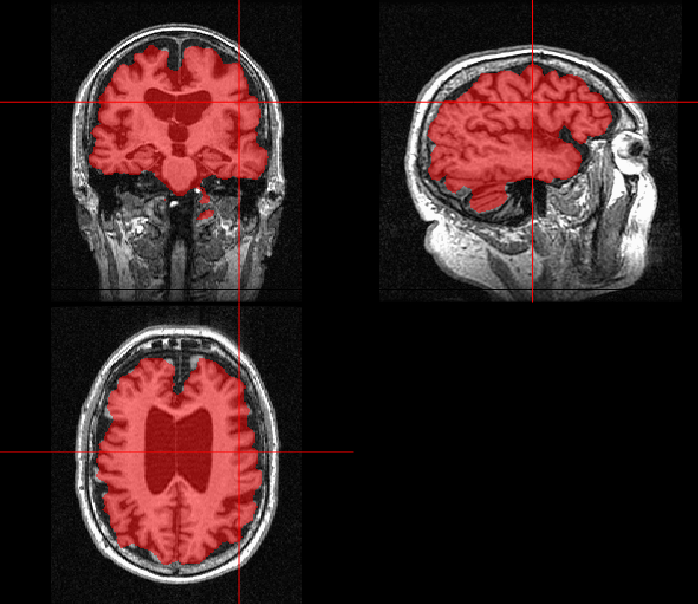

If the voxel frequency vs. intensity plot is observed, the three different tissue classes are apparent as three Gaussian peaks. The lowest intensity peak corresponds to Cerebrospinal Fluid (CSF), whereas the subsequent peaks determine the intensity peaks of grey matter (GM) and white matter (WM). A probability distribution for each tissue class is assigned such that 𝒫𝒫\mathcal{P}(CSF) is near zero intensity levels; 𝒫𝒫\mathcal{P}(GM) is of low to moderate levels of intensity; 𝒫𝒫\mathcal{P}(WM) is of moderate to high levels of intensity. Spatial neighbourhood information or the HMRF model is used to segment each tissue class as simple classifiers like K-means do not use spatial entropy information, and we need a proper balance. The log probability model can be represented as logp(intensity)+βlogp(MRF)𝑙𝑜𝑔𝑝𝑖𝑛𝑡𝑒𝑛𝑠𝑖𝑡𝑦𝛽𝑙𝑜𝑔𝑝𝑀𝑅𝐹logp(intensity)+\beta logp(MRF), where β𝛽\beta is user-adjustable. Output files of the FAST algorithm provide three separate probability maps for corresponding tissue classes: pve0𝑝𝑣subscript𝑒0pve_{0}, pve1𝑝𝑣subscript𝑒1pve_{1}, and pve2𝑝𝑣subscript𝑒2pve_{2} for CSF, GM and WM, respectively. The ortho2𝑜𝑟𝑡𝑜2ortho2 function in R is used to overlay the probability maps on the pre-processed T1 weighted image, as shown in Fig 6.

Refer to caption

(a)

(b)

(c)

Figure 6: Segmentation of tissue classes of sample AD patient slice: (a)Cerebrospinal fluid (b) Grey Matter (c) White Matter

The changes in volumes of each patient for the tissue classes across three or four visits are observed and reported. These changes can be considered as relevant imaging features to understand the prognosis of Alzheimer’s disease.